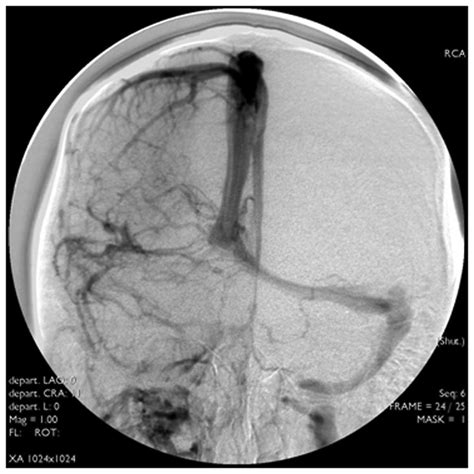

Imaginea de mai sus ilustrează un RMN sagital T1 al regiunii hipofizare, probabil evidențiind o glandă anormal mărită, prin disproporția vizuală în raport cu șaua turcească și conturul convex superior.

- Efecte mecanice de masă:

- Extensie supraselară, compresie a chiasmei optice (risc vizual crescut).

- Extensie paraselară sau remodelare osoasă a șeii turcești.